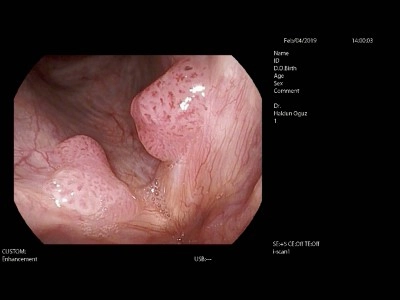

Papillomlar tipik olarak çok sayıda siğil benzeri lezyonlar şeklinde ortaya çıkarlar. Üst hava yolunun herhangi bir yerinde görülebilmekle birlikte, olguların %95’i gırtlakta görülür. Gırtlaktaki patolojiler genellikle gerçek ses tellerini ve yalancı ses tellerini (ventriküler bantlar) etkiler. Hastaların %2-15’inde soluk borusu (ses tellerinin daha altında yer alır) ve yemek borusunda da hastalık görülebilir. Hastaları hekime getiren ilk şikayet genellikle ses kısıklığıdır. Soluk alma verme sırasında hırıltı, öksürük, nefes alma güçlüğü ile yemek yerken veya yutarken olan ağrı da şikayete neden olabilir. Ses teli papillomu olan iki ayrı hastamızın muayene videolarını aşağıda izleyebilirsiniz.